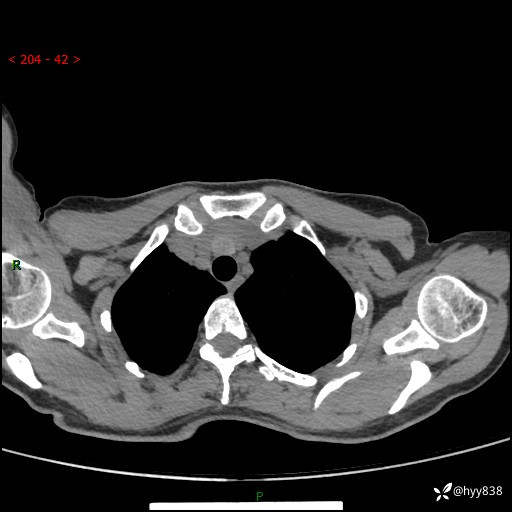

增强动脉期+静脉期